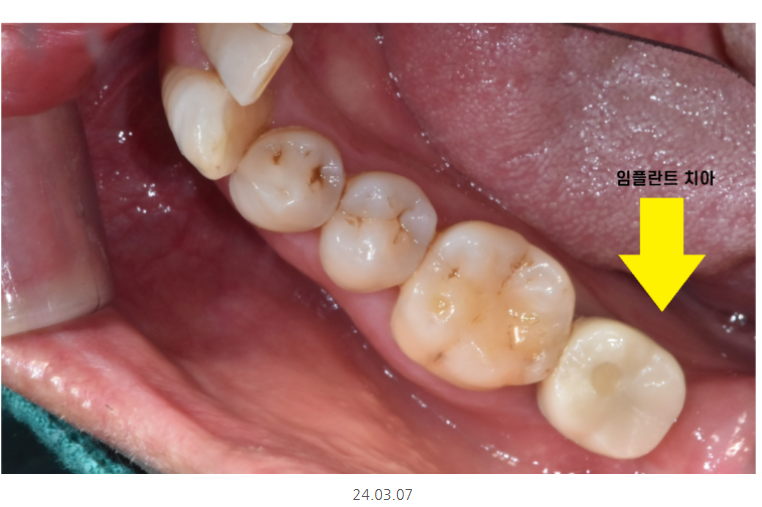

머리가 완성되고 바로 완전하게 안붙여 드렸는데요.

처음에는 임시로 약하게 붙여드렸습니다.

테스트 하는 기간을 거쳤습니다.

식사해보시고 불편하시면

수정이 들어가야하니까요~

식사해보시고 참으로 편안하다는 말씀을 해주셔서

뿌듯했습니다. ㅎㅎ

임시로 붙였던걸 떼고

단단한 접착제로 붙여 치료를 마무리 해드렸습니다.